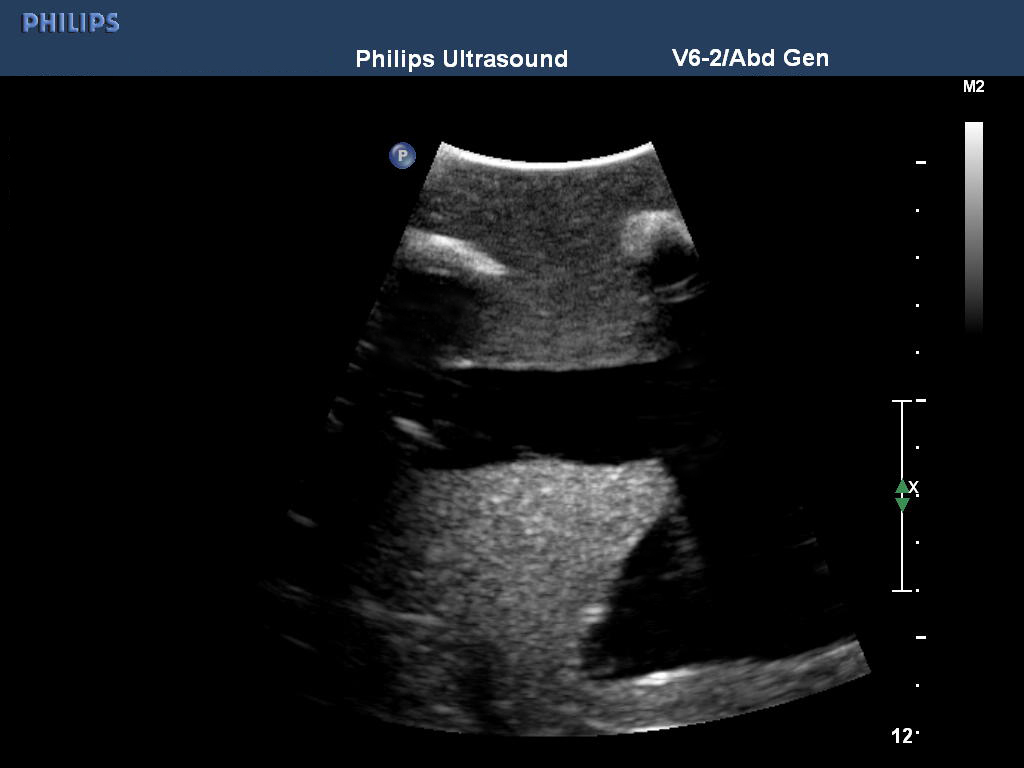

模型能够与任何超声影像检查设备连接使用,是练习提升经超声引导进行胸腔穿刺的理想模型。同时此模型还可用于练习非超声引导条件下胸腔穿刺,非超声引导胸廓造口术。